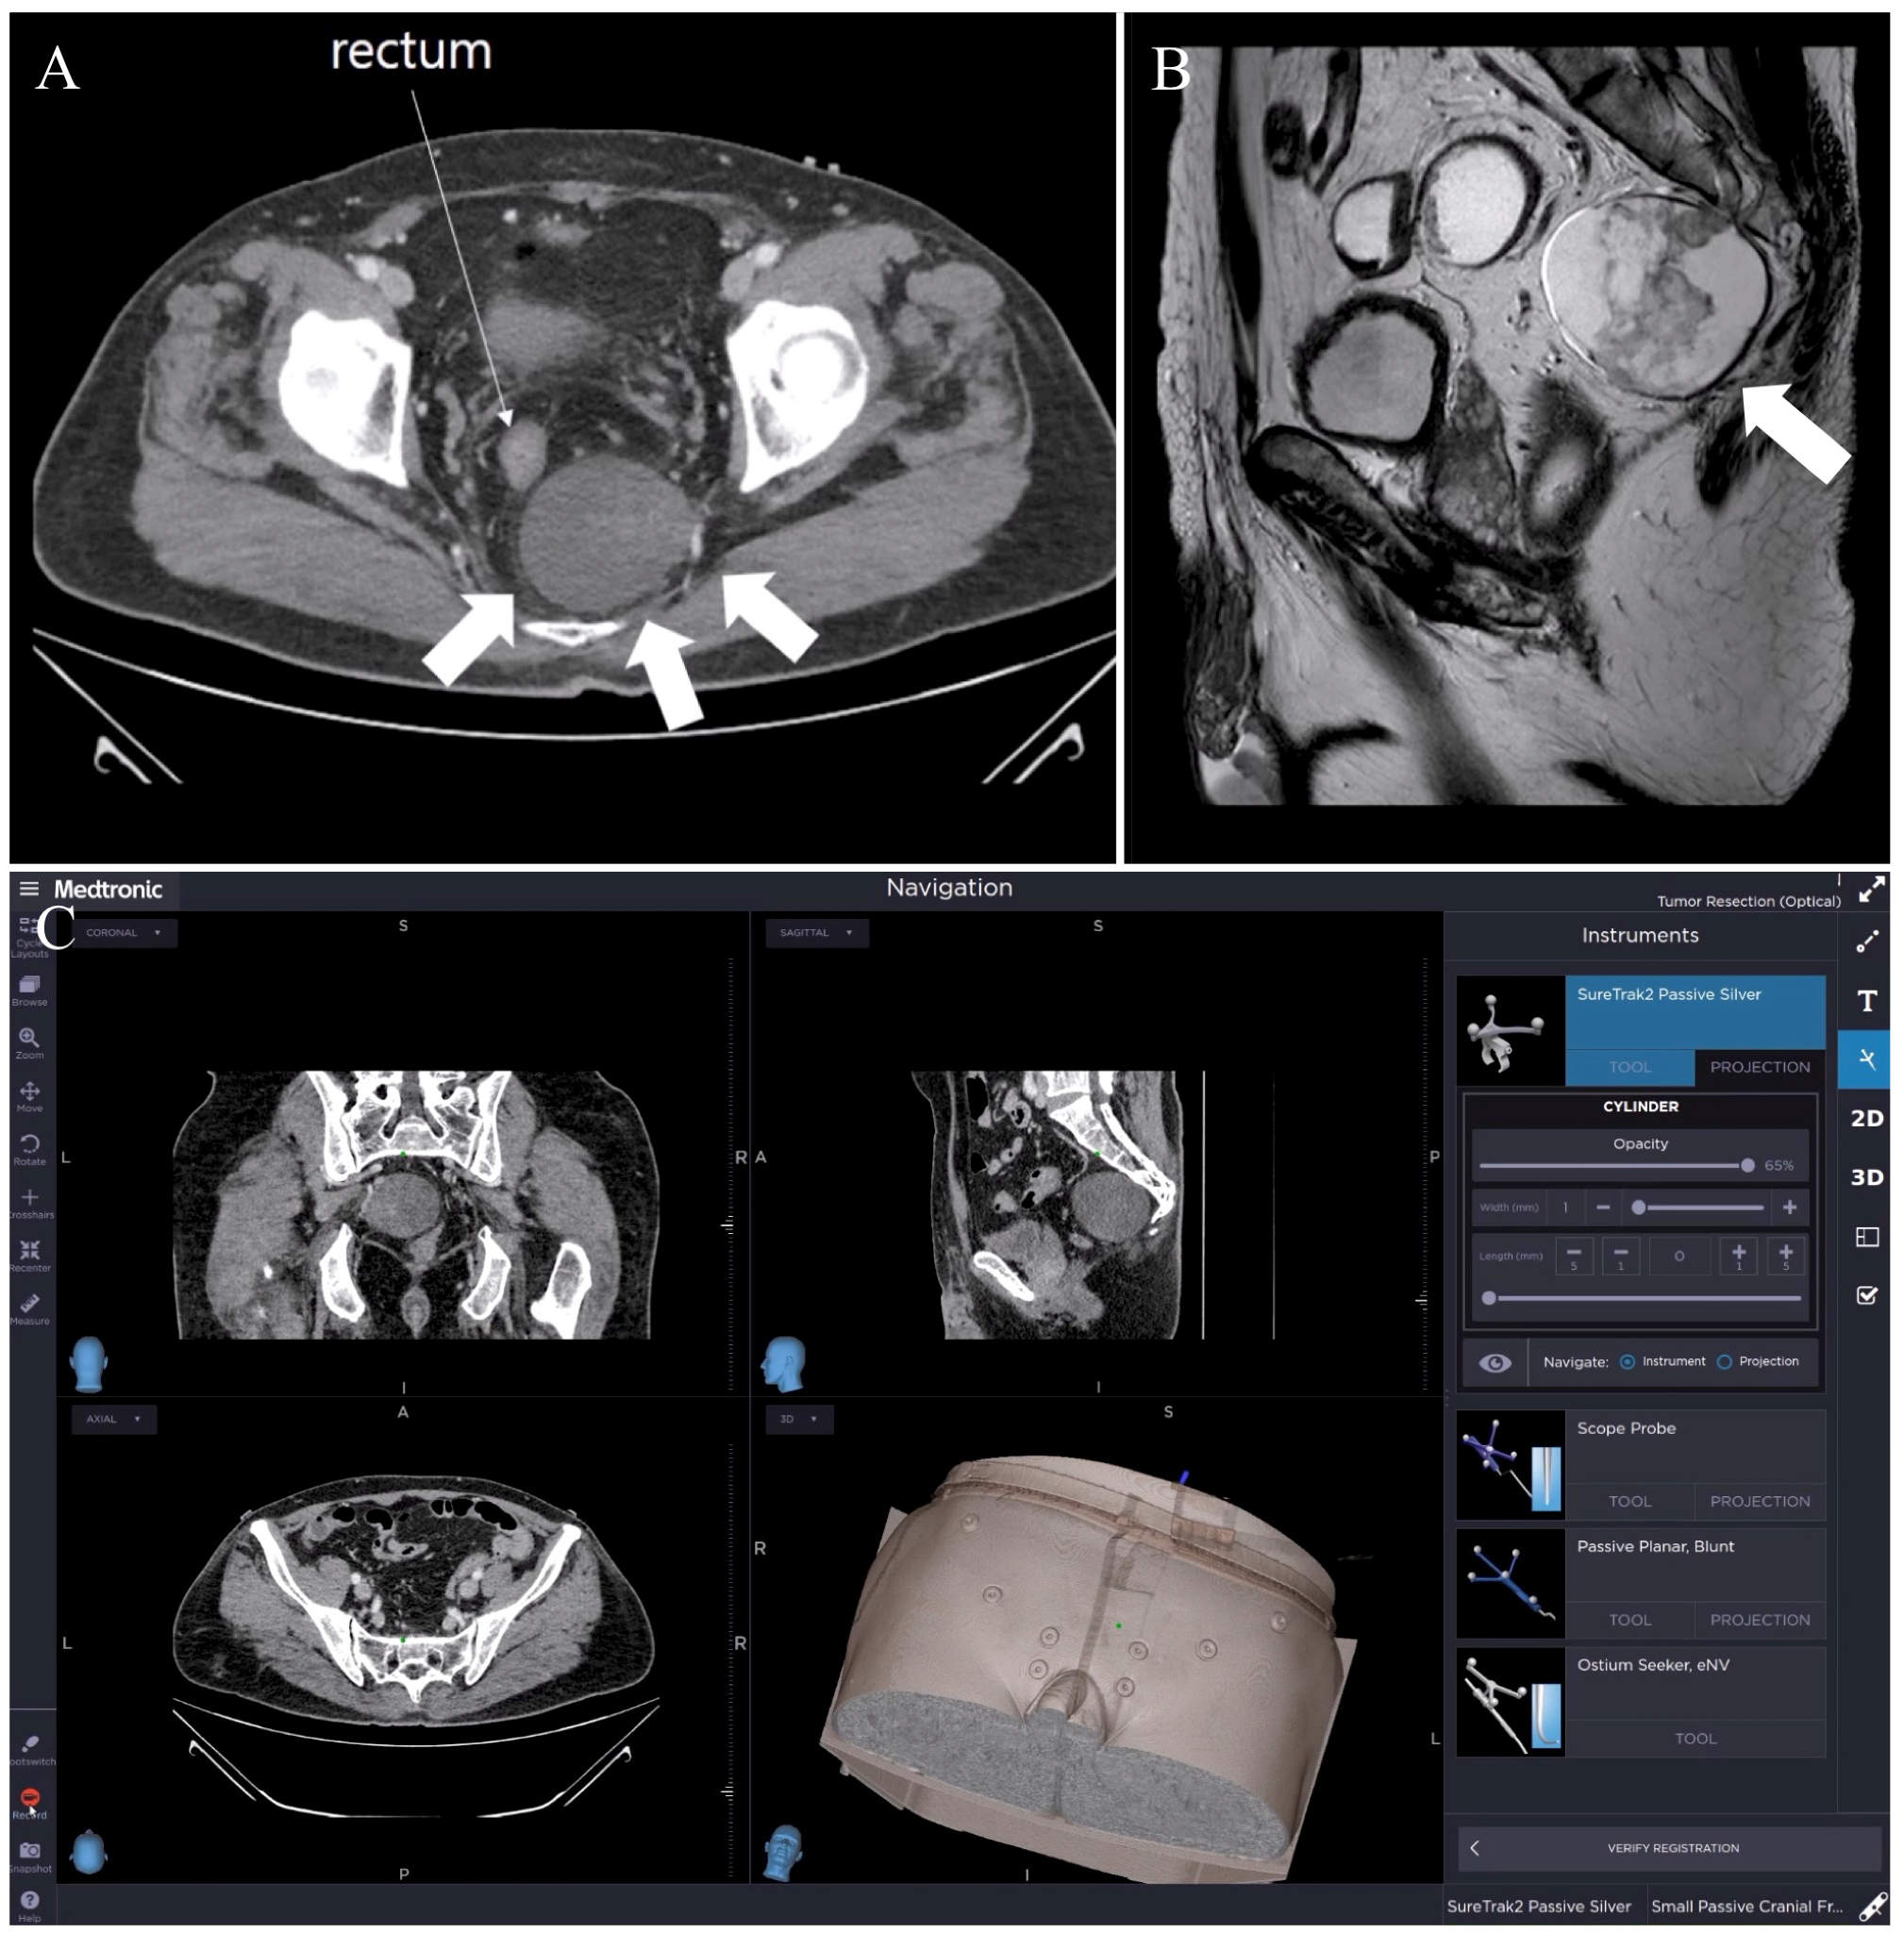

3.1. Case 1: Retro-Rectal Tumor